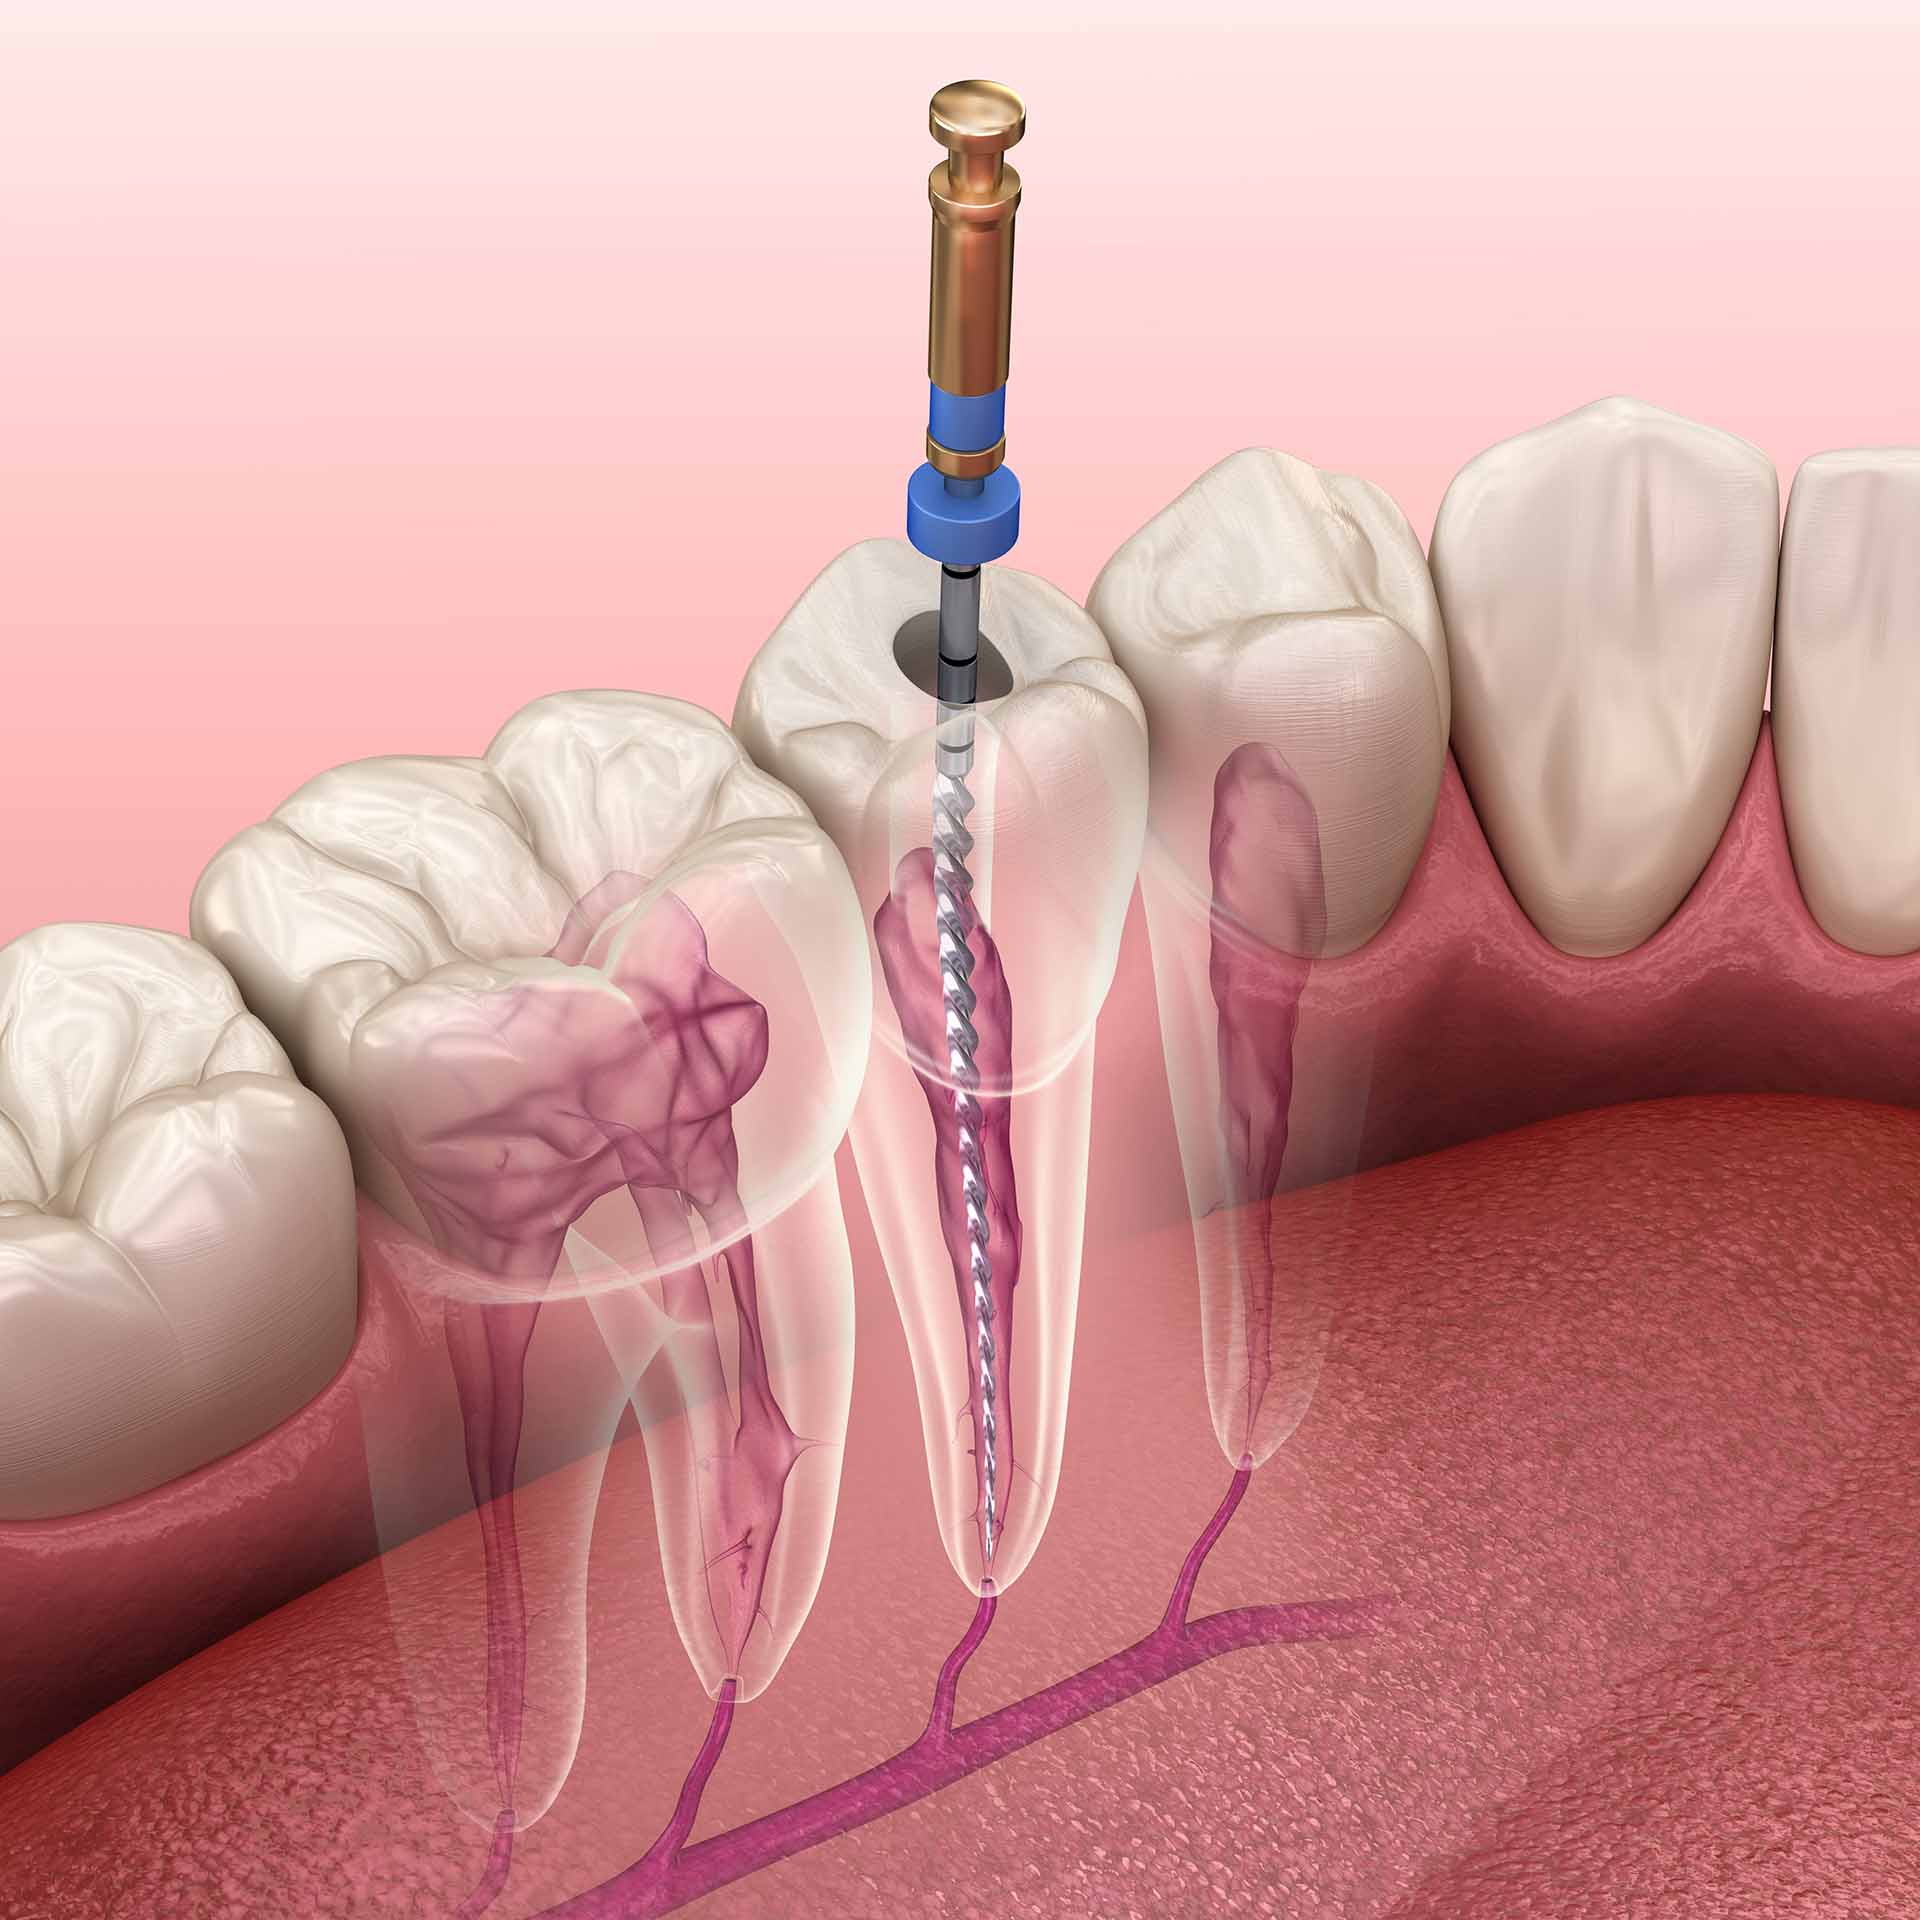

General Dentistry

General dentistry plays a crucial role in maintaining overall oral health, offering essential services like routine cleanings, exams, and treatments that prevent dental issues and promote a lifetime of healthy smiles.